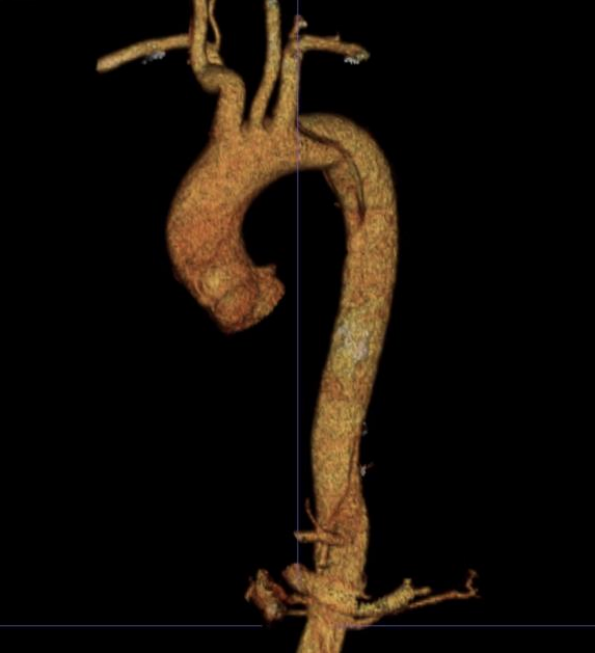

★病例1

28岁男性,急性复杂型B型AD,急诊TEVAR治疗